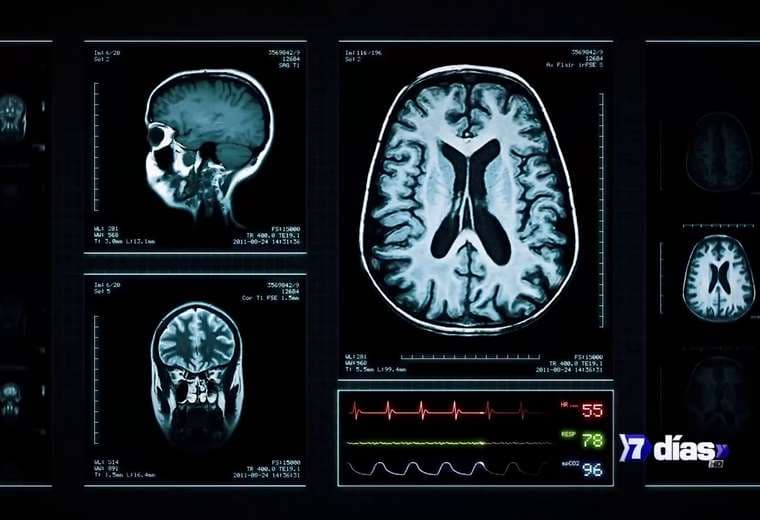

El mal que aqueja a Bruce Willis

La demencia frontotemporal genera cambios en la personalidad y dificultad para hablar, lo cual la hace una enfermedad muy difícil de enfrentar.

Alguna vez fue visto como un policía que se enfrentó y venció a terroristas, como un experto en perforación petrolera que salvó al mundo. Hoy, la súper estrella Bruce Willis sufre un tipo de demencia que genera cambios drásticos en la personalidad y dificultad para hablar: Demencia Frontotemporal.